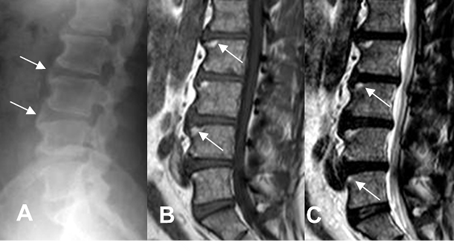

Fig 59 A. Lesiones Romanus.

A, B y C: Rx lateral. Esquinas brillantes en diferentes estados de evolución, por esclerosis de lesiones Romanus, en los cuerpos vertebrales.

Fig 59 B. Lesiones Romanus.

A: RM sagital en T1 y B: RM sagital en T2. Lesión en la esquina posterior del cuerpo vertebral cervical, hipointenso en T1 e hiperintenso en T2, por lesión Romanus de evolución aguda.

Fig 59 C. Lesiones Romanus.

A: RM sagital en T1 y B: RM sagital en T2. Lesiones en las esquinas de las vértebras hipointensas en T1 e hiperintensas en T2, por lesiones Romanus de evolución aguda. Hay otras lesiones hiperintensas en ambas secuencias, por evolución subaguda.